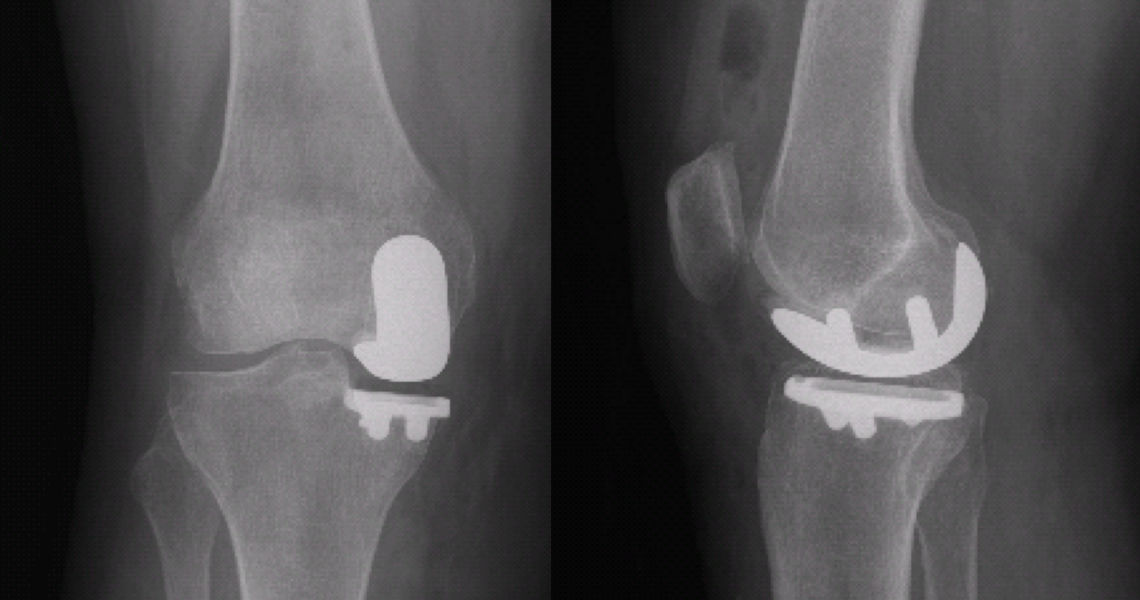

Kısmi (unikondiler, parsiyel) diz protezi uygulaması sırasında dizin sadece aşınmış olan yüzeyleri değiştirilir. Kısmi diz protezleri, sıklıkla dizin iç yarısı için uygulanır ama dış yarısı ve diz kapağının altında da başarı ile uygulanırlar (Resim 1). Dizin tamamının aşınmış olduğu durumlar ve ilerleyici romatoid artrit (iltihaplı romatizma), ankilozan spondilit gibi hastalıklarda kısmi protezler uygun değildir. Dizin sadece aşınmış olan kısımlarına yüzey kaplaması yapılır ve sağlam taraftaki menisküs, eklem kıkırdağı ve bütün diz bağları korunur. Bu da total (tam) diz protezine kıyasla daha normal bir diz hissi, daha kolay ameliyat sonrası iyileşme ve daha iyi eklem hareket açıklığı elde edilmesini sağlar. Hastaların günlük yaşam veya işe dönmeleri çok daha kısa sürede gerçekleşir. Robotik kısmi diz protezleri ile dizin aşınma öncesi sağlıklı durumu, büyük bir doğruluk ve yumuşak doku dengesi sağlanacak şekilde oluşturulur. Robotik cerrahi önce kısmi diz protezleri ile başlamış ve sonrasında total diz ve kalça sistemleri geliştirilmiştir. Bu nedenle dünyada en fazla ve uzun süre takipli deneyim kısmi protezlerledir.

Resim 1: Dizin sadece iç yarısı aşınmış olan bu hasta kısmi (unikondiler) protez için uygun.

Ameliyatın ertesi gününde, aktif ve yardımlı diz hareketleri bir fizyoterapist gözetiminde başlanır. Bunun için fizyoterapist yardımı veya sürekli pasif hareket (continious passive motion, CPM) cihazı ile istenen açılarda diz hareketleri yapılır. Tutunarak hemen merdiven çıkıp inmeye başlayabilirsiniz, bu eğitim fizyoterapist tarafından verilecektir. İkinci günde röntgen kontrolünüz yapılır (Resim 9).

Resim 9: Resim 1’deki hastanın robotik unikondiler protez uygulandıktan sonraki röntgen kontrolü.